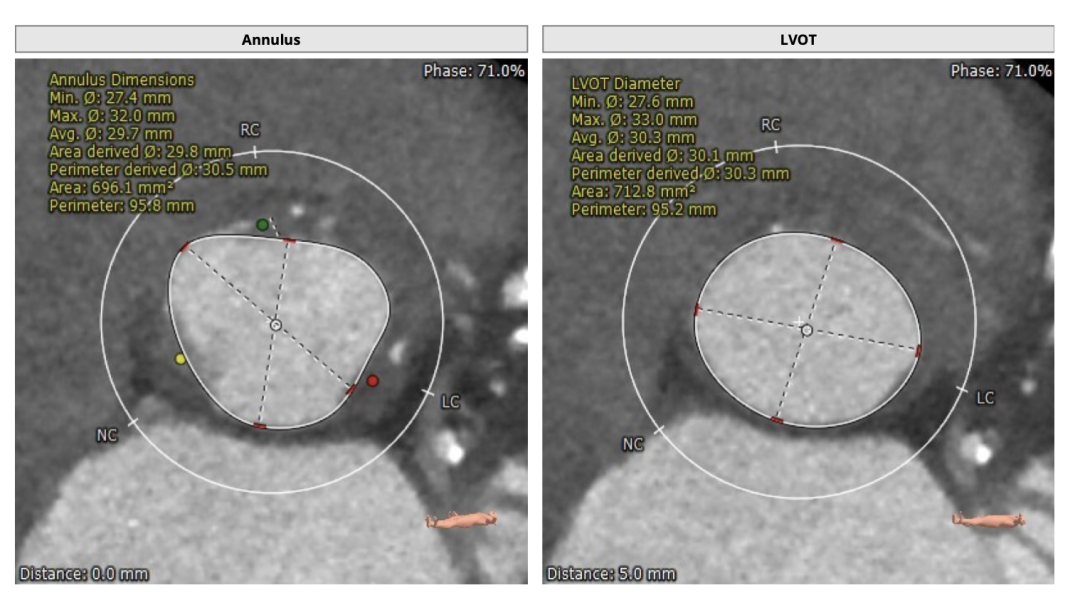

瓣环直径:30.5mm,左室流出道直径:30.3mm

主动脉窦:36.0*37.9*42.1mm,STJ:29.6mm